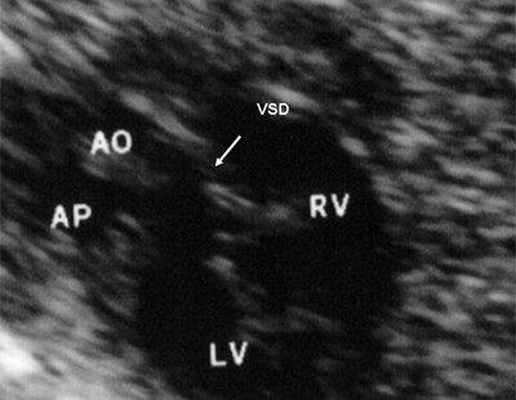

Трехмерно реконструированные перспективы у пациента с врожденной корригированной транспозицией, большим дефектом межжелудочковой перегородки (VSD) и рудиментарным правым желудочком (RV).

При реконструкции сечения по зеленой оси получается кадр в центре, на котором хорошо видно параллельное отхождение РА и восходящей части аорты (АоА).

В равной степени это относится к дефекту межжелудочковой перегородки (рис. 6), простой форме транспозиции магистральных сосудов (рис. 7, 8), транспозиции магистральных сосудов с дефектом межжелудочковой перегородки (синдром Тауссиг - Бинга) (рис. 9), общему желудочку (рис. 10), общему артериальному стволу (рис. 10), двойному отхождению сосудов от одного из желудочков сердца (рис. 11).

Рис. 6. Дефект межжелудочковой перегородки. Длинная ось сердца. Стрелками показан дефект межжелудочковой перегородки.

LV и RV - левый и правый желудочек, АР - легочная артерия, АО - аорта, VSD - дефект межжелудочковой перегородки.